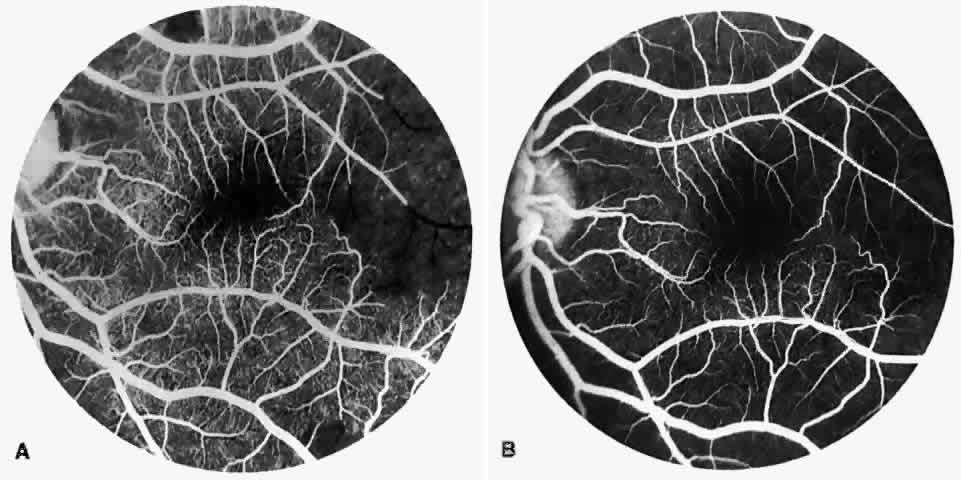

Dilation and tortuosity of the retinal veins was one of the first recognized abnormalities of sickle cell eye disease. Although it is not pathognomonic of sickle cell disease, it reportedly occurs in up to 47% of patients with homozygous sickle cell anemia and 32% of patients with SC disease (Fig. 4).70 The significance of this venous tortuosity is unknown, and the incidence does not appear to be related to age.71

Fig. 4. A. Generalized vascular tortuosity, predominantly venous, in a patient with homozygous sickle cell anemia. B. Localized macular venous tortuosity in a patient with SC disease.